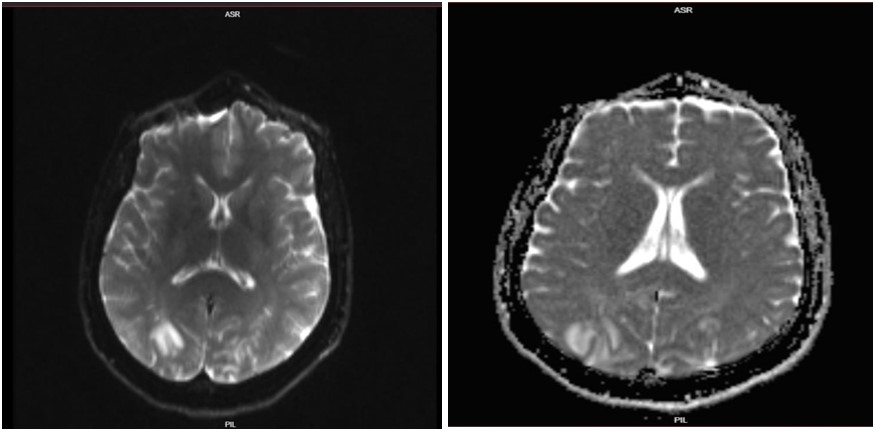

Due to the persistence of neurological symptoms, a brain MRI (Fig. 2) was also conducted. The MRI findings included:

- Multifocal areas of abnormal signal intensity involving both the occipital and parietal lobes, distributed cortically and subcortically, causing gyral swelling

- Hyperintense lesions on T2-weighted and FLAIR sequences, consistent with vasogenic edema

- No restricted diffusion or susceptibility artifact, indicating absence of infarction or hemorrhage

- No midline shift

- Normal brainstem, cerebellum, and ventricular system with no hydrocephalus

- An incidental 1 cm retention mucous cyst in the left maxillary sinus

- Remaining paranasal sinuses and mastoid air cells were well aerated

These MRI findings were diagnostic of Posterior Reversible Encephalopathy Syndrome (PRES).

Figure 2: MRI image showing cortical/subcortical lesions in the occipital lobes.

PRES is typically associated with acute, severe hypertension and is most commonly observed in women with preeclampsia and eclampsia, as well as in those with other conditions associated with elevated blood pressure, such as renal disease and immunosuppressive therapy. The condition is thought to result from a breakdown of the blood-brain barrier (BBB), leading to vasogenic edema, particularly in the posterior regions of the brain. The occipital lobes are most commonly affected, which explains the characteristic visual disturbances that occur in a significant proportion of patients with PRES (Marra et al., 2014). In this case, the patient developed visual loss, which was likely due to edema affecting the occipital cortex. The CT scan findings of bilateral hypodense areas in the subcortical white matter and the mild brain edema are consistent with the pathophysiology of PRES.

Neuroimaging, particularly MRI and CT scans, plays a crucial role in diagnosing PRES and differentiating it from other neurological conditions that can arise in the setting of severe hypertension, such as intracranial hemorrhage or stroke. In this case, the CT brain scan revealed bilateral hypodense areas in the subcortical white matter of the occipital and parietal lobes, a finding that is highly suggestive of PRES. While CT can identify structural changes associated with PRES, MRI is generally considered more sensitive and can provide more detailed information regarding the extent and location of the edema. The absence of intracranial hemorrhage, territorial infarction, and space-occupying lesions in the imaging further supported the diagnosis of PRES and helped exclude other potential causes of the patient’s neurological symptoms.